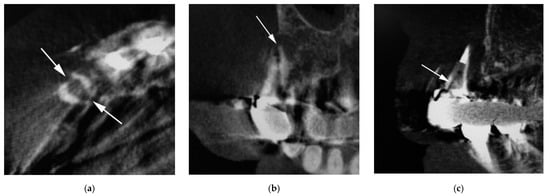

Characteristics of 36 vertical root fractures are shown in Table 2. All the vertically fractured teeth were nontraumatized teeth. The occurrence of vertical root fracture was not different among metal core, composite resin core, and no core (χ2 (2) = 1.17, p = 0.558). The number of vertical root-fractured teeth differed significantly among the anterior, premolar, and molar teeth (χ2 (2) = 10.50, p = 0.005), and the number of vertical root fractures in premolar teeth was largest. The number of vertical root fractures was significantly different between the bucco-lingual fracture (Figure 1) and mesio-distal fracture (Figure 2) (χ2 (1) = 4.00, p = 0.046), and the number of the bucco-lingual fractures was twice that of the mesio-distal fractures.

Figure 1. Cone-beam computed tomography (CBCT) image of vertical root fractures in endodontically treated teeth (bucco-lingual fracture). (a) Axial image; (b) cross-sectional multiplanar reformation (MPR) image; and (c) parasagittal MPR image. Arrow indicates part of root fracture.

Figure 2. CBCT image of vertical root fractures in endodontically treated teeth (mesio-distal fracture). (a) Axial image; (b) cross-sectional MPR image; (c) parasagittal MPR image. Arrow indicates part of root fracture.